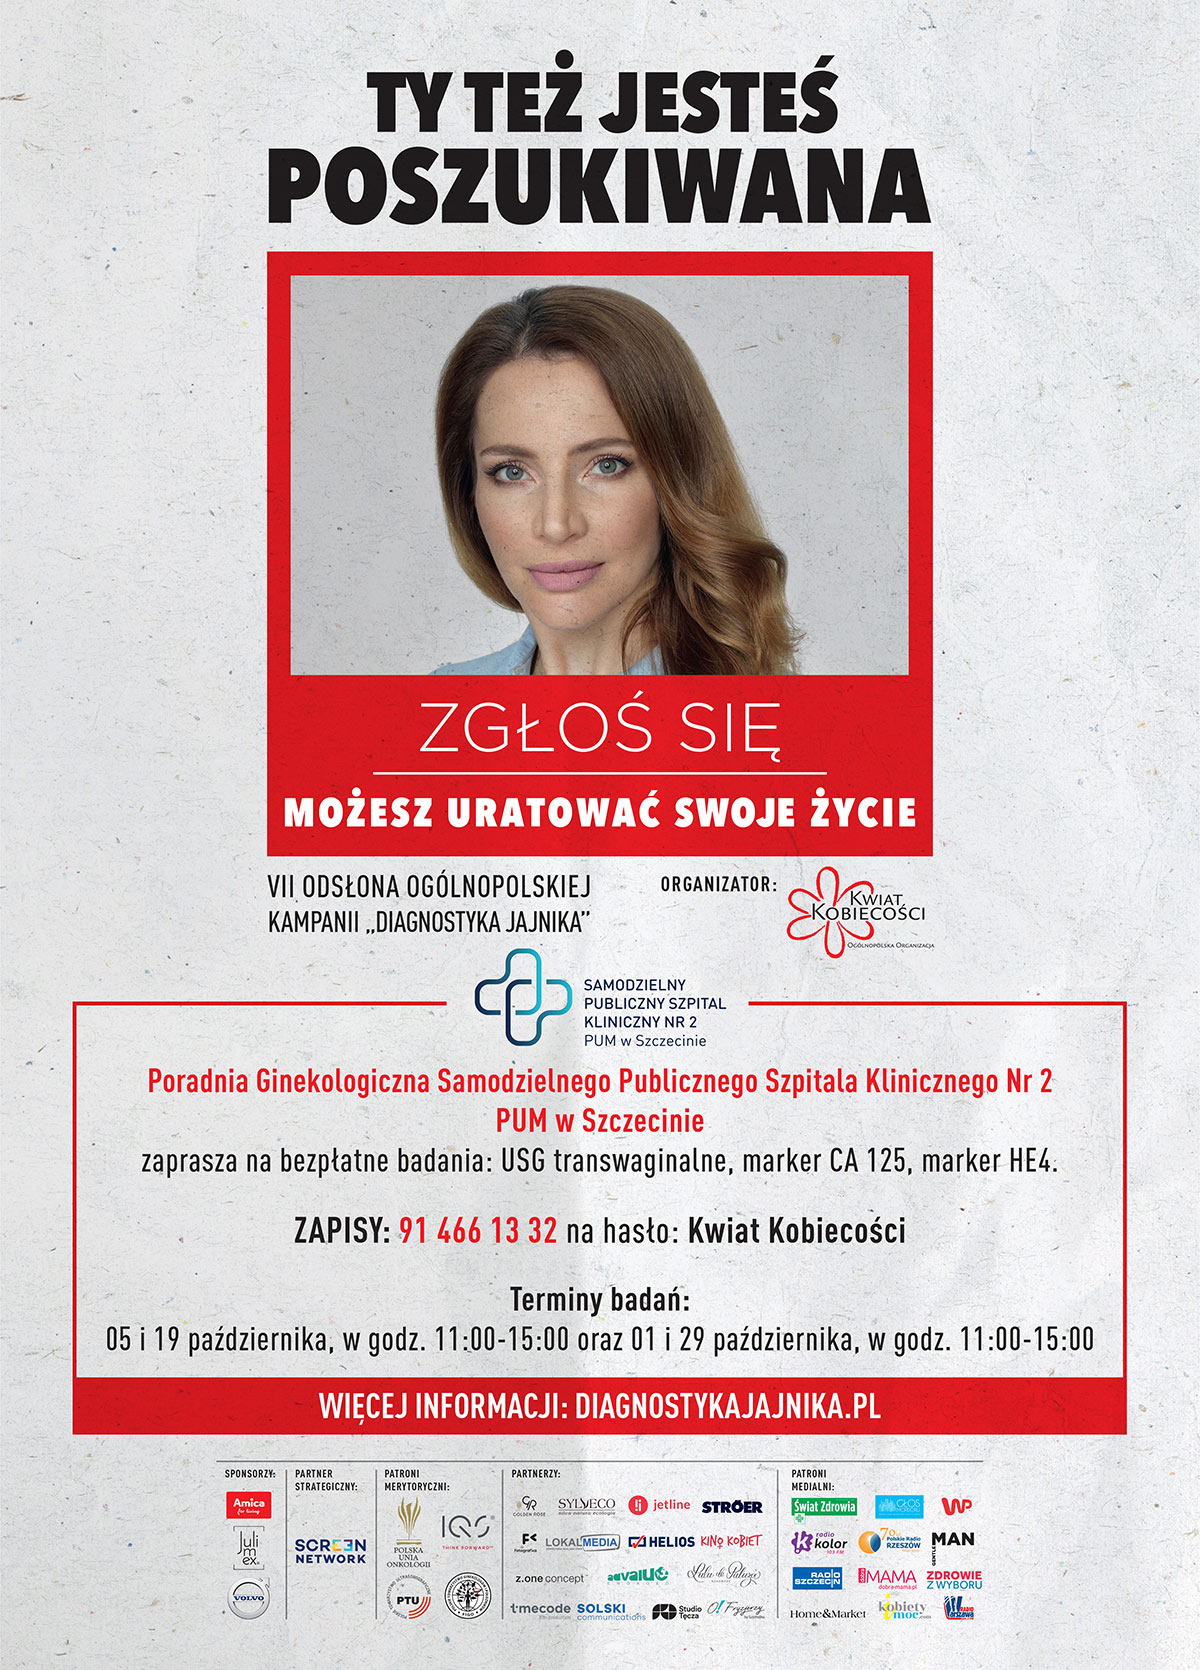

Eksperckie warsztaty ginekologiczno-onkologiczne

2023-09-07Wrzesień jest turkusowym miesiącem świadomości nowotworów ginekologicznych. Z tej okazji Klinika Ginekologii Operacyjnej i Onkologii Ginekologicznej Dorosłych i Dziewcząt naszego szpitala razem z Polskim Towarzystwem Ginekologii Operacyjnej zaprasza na bezpłatne, otwarte spotkania „Dbam o siebie - dbam o swoje zdrowie”. Zapraszamy!

Bardzo dużo do zrobienia jest w zakresie edukacji nt. profilaktyki, diagnozowania, leczenia nowotworów ginekologicznych i kompleksowej opieki nad pacjentkami ginekologicznymi. Lekarze niestety wciąż dostrzegają zbyt niską świadomość kobiet co do możliwości profilaktyki i leczenia tych chorób. Dane mówią same za siebie:

Roczna zachorowalność na nowotwory ginekologiczne w Polsce:

rak endometrium – ok. 6 400 kobiet

rak jajnika – ponad 4 000 kobiet

rak szyjki macicy – 2 400 kobiet

Warsztaty odpowiedzą na pytania: Jakie są metody leczenia tych nowotworów? Na ile rak jajnika, rak szyjki macicy, czy endometrium jest wyleczalny? Jak i gdzie go leczyć? Jaka jest jakość życia po leczeniu? Jak leczenie nowotworów ginekologicznych w Polsce wygląda na tle innych krajów Europy?

W panelach: prelekcje, prezentacje, wykłady, filmy, rozmowy z lekarzami, możliwość zadawania pytań.

„Dbam o siebie - dbam o swoje zdrowie” – KIEDY i GDZIE?

- 9 września (sobota) 2023, godz. 10.00-13.00

- hala widowiskowo-sportowa Netto Arena

- ul. Władysława Szafera 3/5/7, wejście od frontu, przy kasach

- sala konferencyjna, I piętro

CO i KTO?

Prowadzą eksperci – lekarze Kliniki Ginekologii Operacyjnej i Onkologii Ginekologicznej Dorosłych i Dziewcząt Uniwersyteckiego Szpitala Klinicznego Nr 2 PUM w Szczecinie, w tym dr hab. n. med. Anita Chudecka-Głaz, prof. PUM, lekarz kierująca Kliniką, konsultant wojewódzka w dziedzinie ginekologii onkologicznej oraz wiceprezes polskiego Towarzystwa Ginekologii Onkologicznej.